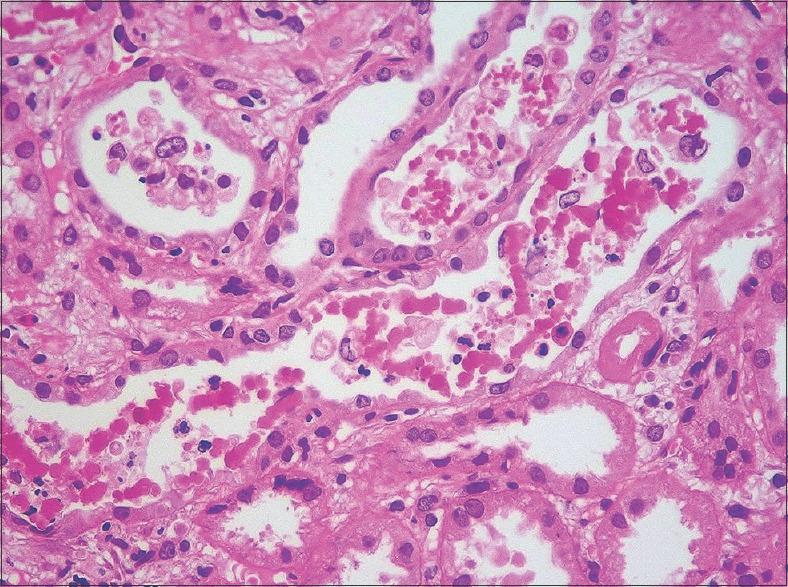

A total of 57 cases of myoglobin cast nephropathy were identified after performing immunohistochemical staining for myoglobin on all renal biopsies with pigment casts. The clinical, laboratory data, histopathological findings and clinical outcome of these cases were evaluated.

The mean patient age was 34.47 years (range 17-77) and the male to female ratio was 6.1:1. All patients presented with acute kidney injury with mean serum creatinine of 8.4 mg/dl (range: 1.7 to 20.8 mg/dl). Rhabdomyolysis was clinically suspected only in 31 patients. Along with myoglobin casts, acute tubular injury was present in all the biopsies. The most frequent conditions associated with myoglobin cast nephropathy in our study were snake envenomation and unaccustomed physical activities. A few activities that caused rhabdomyolysis in our patients were unique to India.